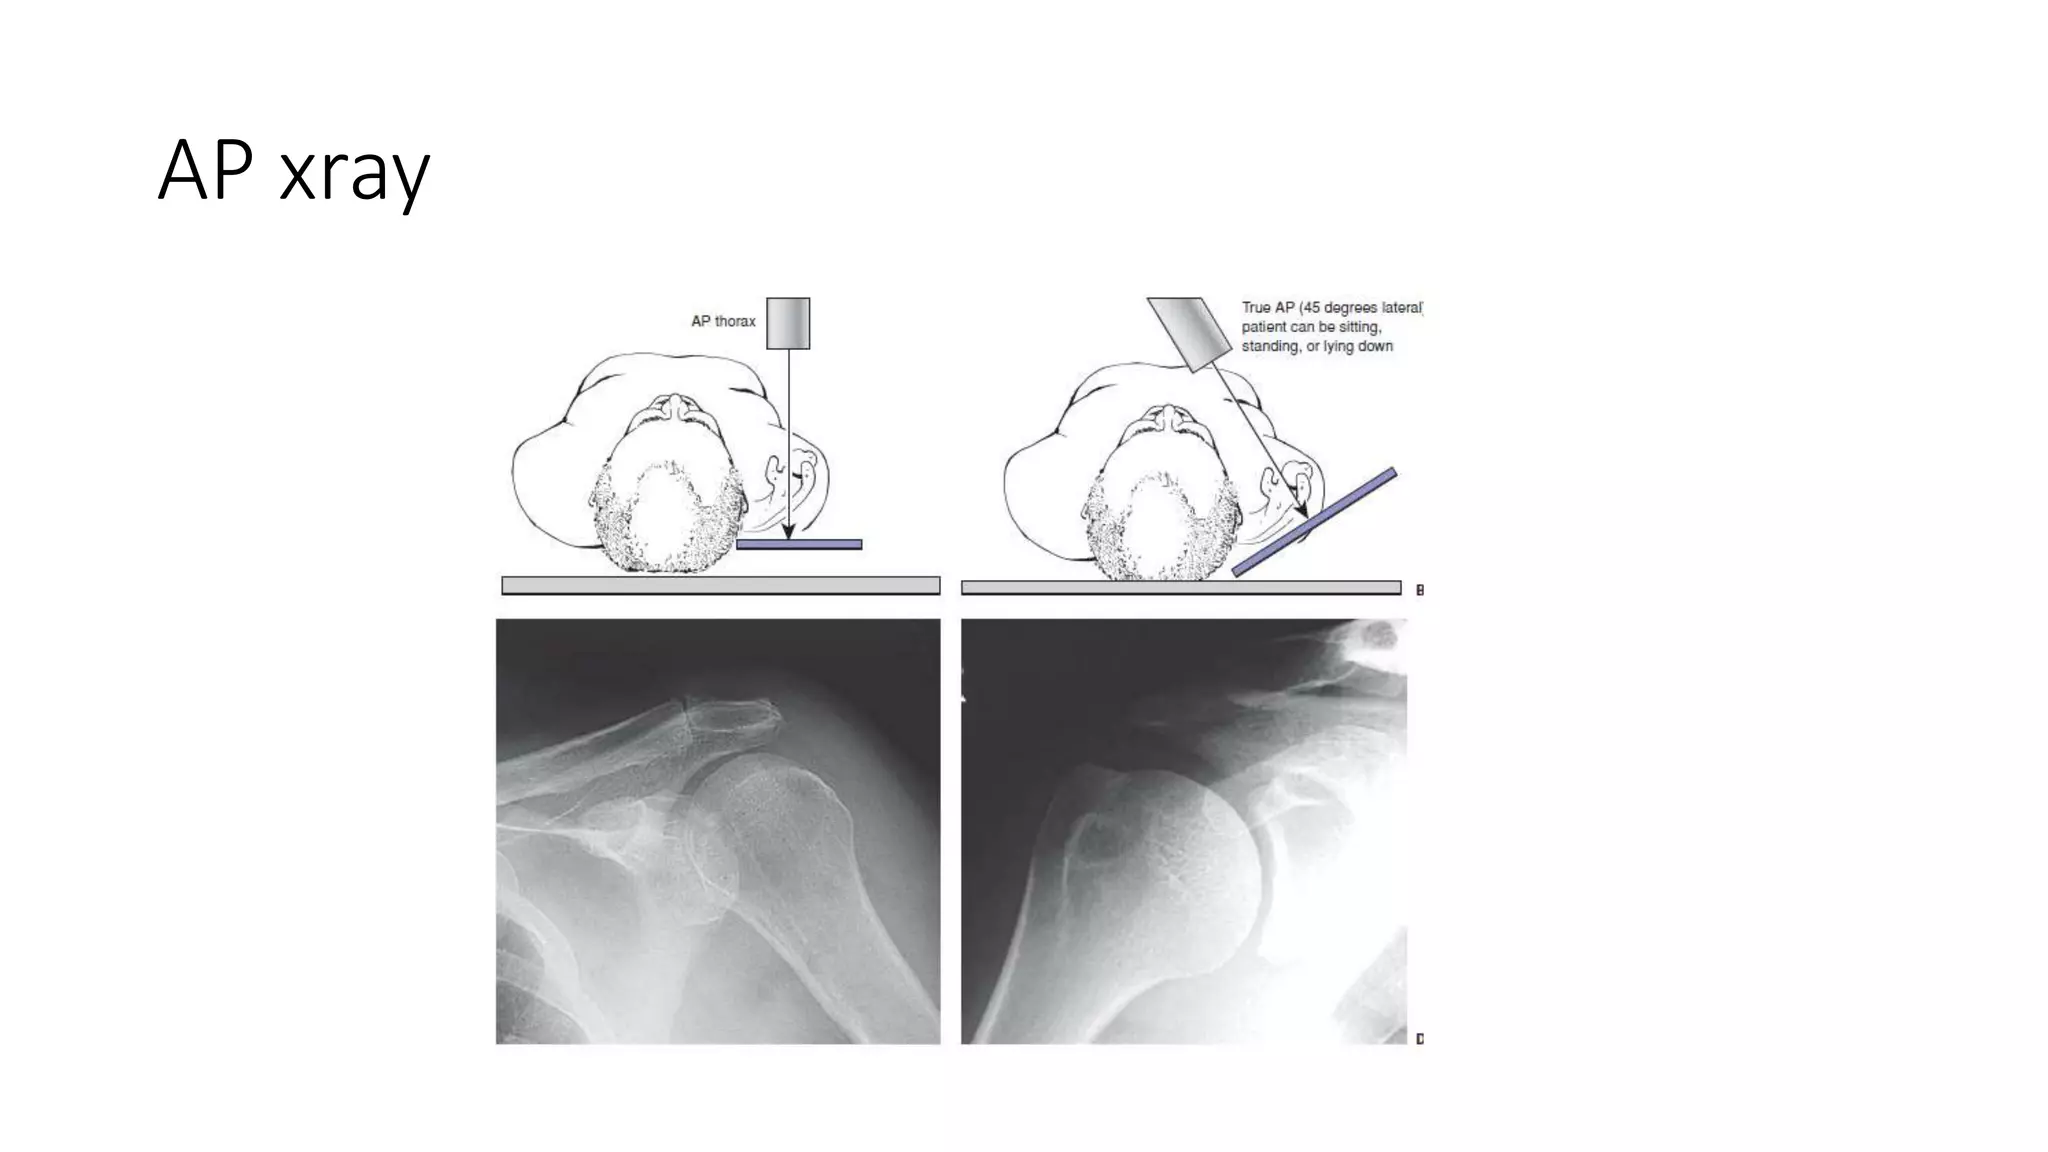

X ray views

• AP chest

• Garshey view

• Axillary lateral

• Trauma lateral view

• Velpeau view

• Scapular Y views

• Stryker view

AP xray